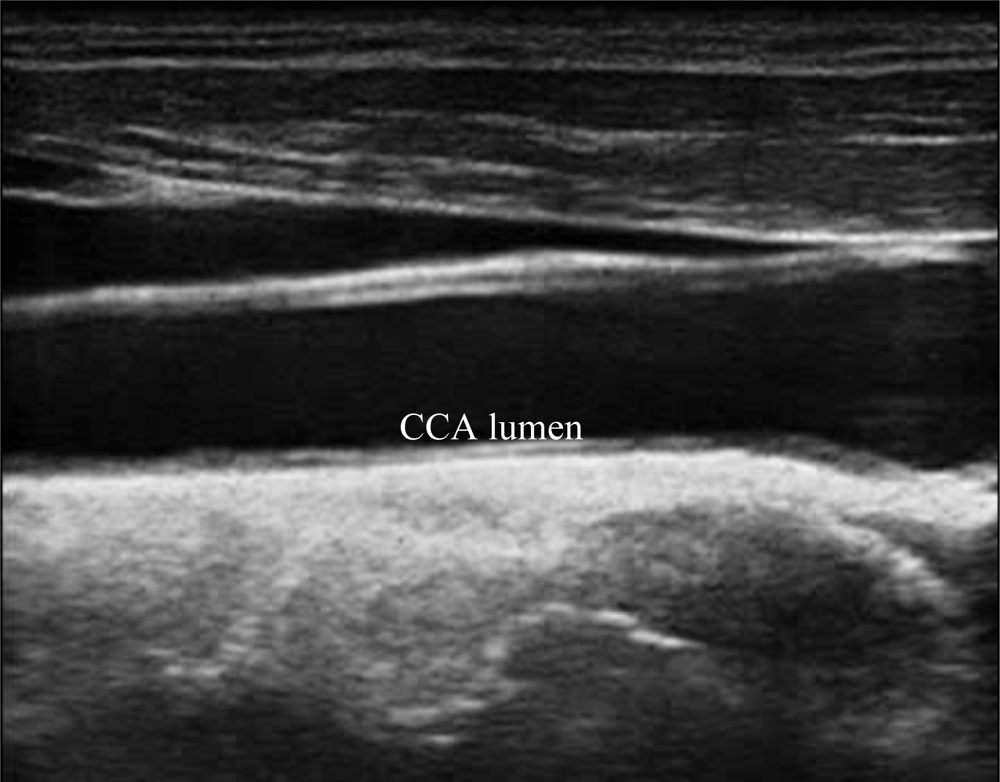

A typical B-mode image is shown in Figure 1. There are plaques on both near and far walls. On the contrary, a typical CCA image without plaque having thin and thick IMT is shown in Figures 2 and 3, respectively. Outlining the boundaries of intima and adventitia is not easy, especially on the near wall. Some features have been studied in previous studies [7,11], in which the most frequently used feature is the gradient of gray-values. From our previous studies [7,14,17], it is found that MacLeod operator combined with some specific enhancement filters are very suitable for feature extraction in intima and adventitia detections.